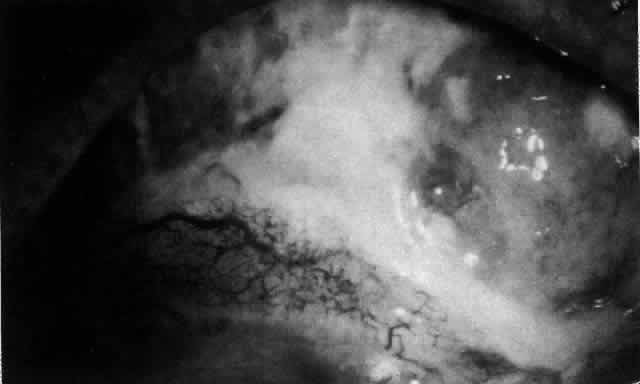

The characteristic features of necrotizing scleritis on fluorescein angiography are hypoperfusion and, eventually, nonperfusion of the vascular networks (Figs. 40 through 43).26 The initial changes are on the venous side of the capillary network; the transit time of the dye increases even if the eye is red and congested. If the disease process persists or has been present for a long time, thrombosis and permanent vaso-occlusive changes occur. These vessels (or the occluded capillary network) are bypassed by the opening of anastomotic channels. New vessels in a granuloma give rise to deep intrascleral leakage of dye (see Fig. 43). Conjunctival and episcleral involvement by the destructive change is late but is always preceded by vaso-occlusive changes that can sometimes be detected with use of the red-free light on the slit lamp (Figs. 44 and 45).

Fig. 40. Early necrotizing scleritis. There is characteristic yellow discoloration of the sclera underlying the conjunctiva at a point of necrosis. In this instance a small filament of tissue has penetrated the conjunctiva.

Fig. 41. Late stage of fluorescein angiogram adjacent to the site of necrosis in the same patient as in Figure 40. Although the eye is uniformly congested, the area near the necrosis shows vascular shutdown, whereas the rest of the conjunctiva and episclera is normally perfused.

Fig. 42. Late arterial phase of fluorescein angiogram in a patient with necrotizing scleritis. All the vessels except the main trunk and the vessels around the limbal perforating vessels are occluded and remain unperfused throughout the angiogram.

Fig. 43. Late venous phase of angiogram of a patient with necrotizing scleritis showing late deep leakage from vessels on the surface of the sclera and leakage of the capillary network at the limbus and the vessels draining it, together with poor or absent perfusion of the remaining vessels.